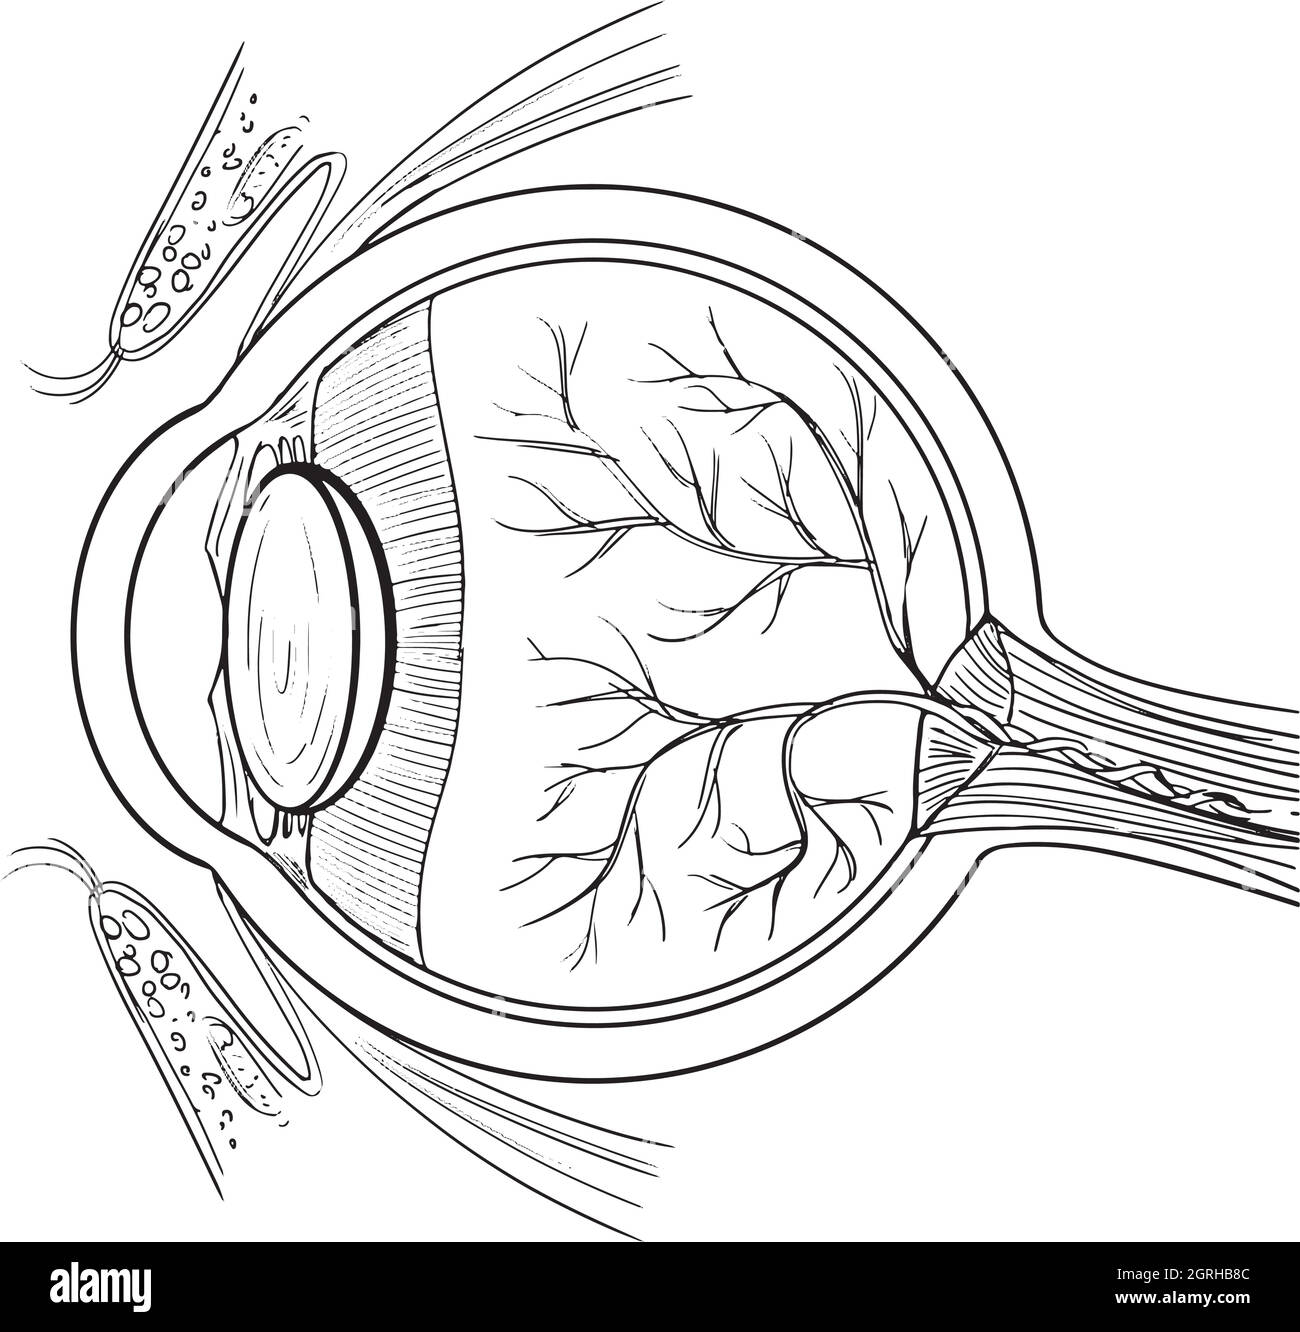

Anatomie de l'œil humain Illustration de Vecteurhttps://www.alamyimages.fr/image-license-details/?v=1https://www.alamyimages.fr/anatomie-de-l-oeil-humain-image444778332.html

Anatomie de l'œil humain Illustration de Vecteurhttps://www.alamyimages.fr/image-license-details/?v=1https://www.alamyimages.fr/anatomie-de-l-oeil-humain-image444778332.htmlRF2GRHB8C–Anatomie de l'œil humain